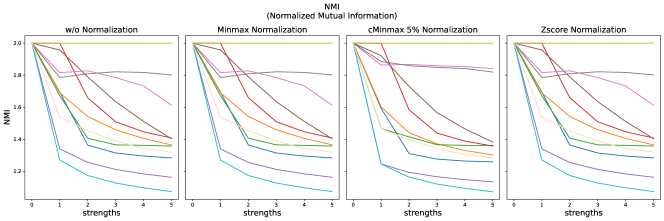

The results for all strengths are given in Figs. A.1-A.4. In Tab. 5 - 8, the results for distortions of maximal strength (s=5) are summarized.

For all applied distortions, all reference metric scores monotonously measure lower similarity for increasing distortion strengths.

Without applying any normalization, all metrics beside NMI are very sensitive to intensity shifts (see Tab. 5). However, with any normalization method, intensity shifts are fully compensated, and all metrics measure perfect similarity.

Across all normalization methods, all metrics are very sensitive to translation and not very sensitive to replace artifacts.

Gaussian noise is better detected with Minmax normalization, while stripe artifacts seem to be less detected with Zscore normalization.

The segmentation scores (see Tab. 5, and Fig. A.4) for all three classes are very similar. Intensity shift has no effect due to preprocessing with z-score normalization. The effect of elastic deforms and ghosting artifacts on the segmentation are very limited. Gaussian noise and stripe artifacts most strongly impair segmentation. Translated segmentations have decreasing overlap and thereby very low DICE scores.